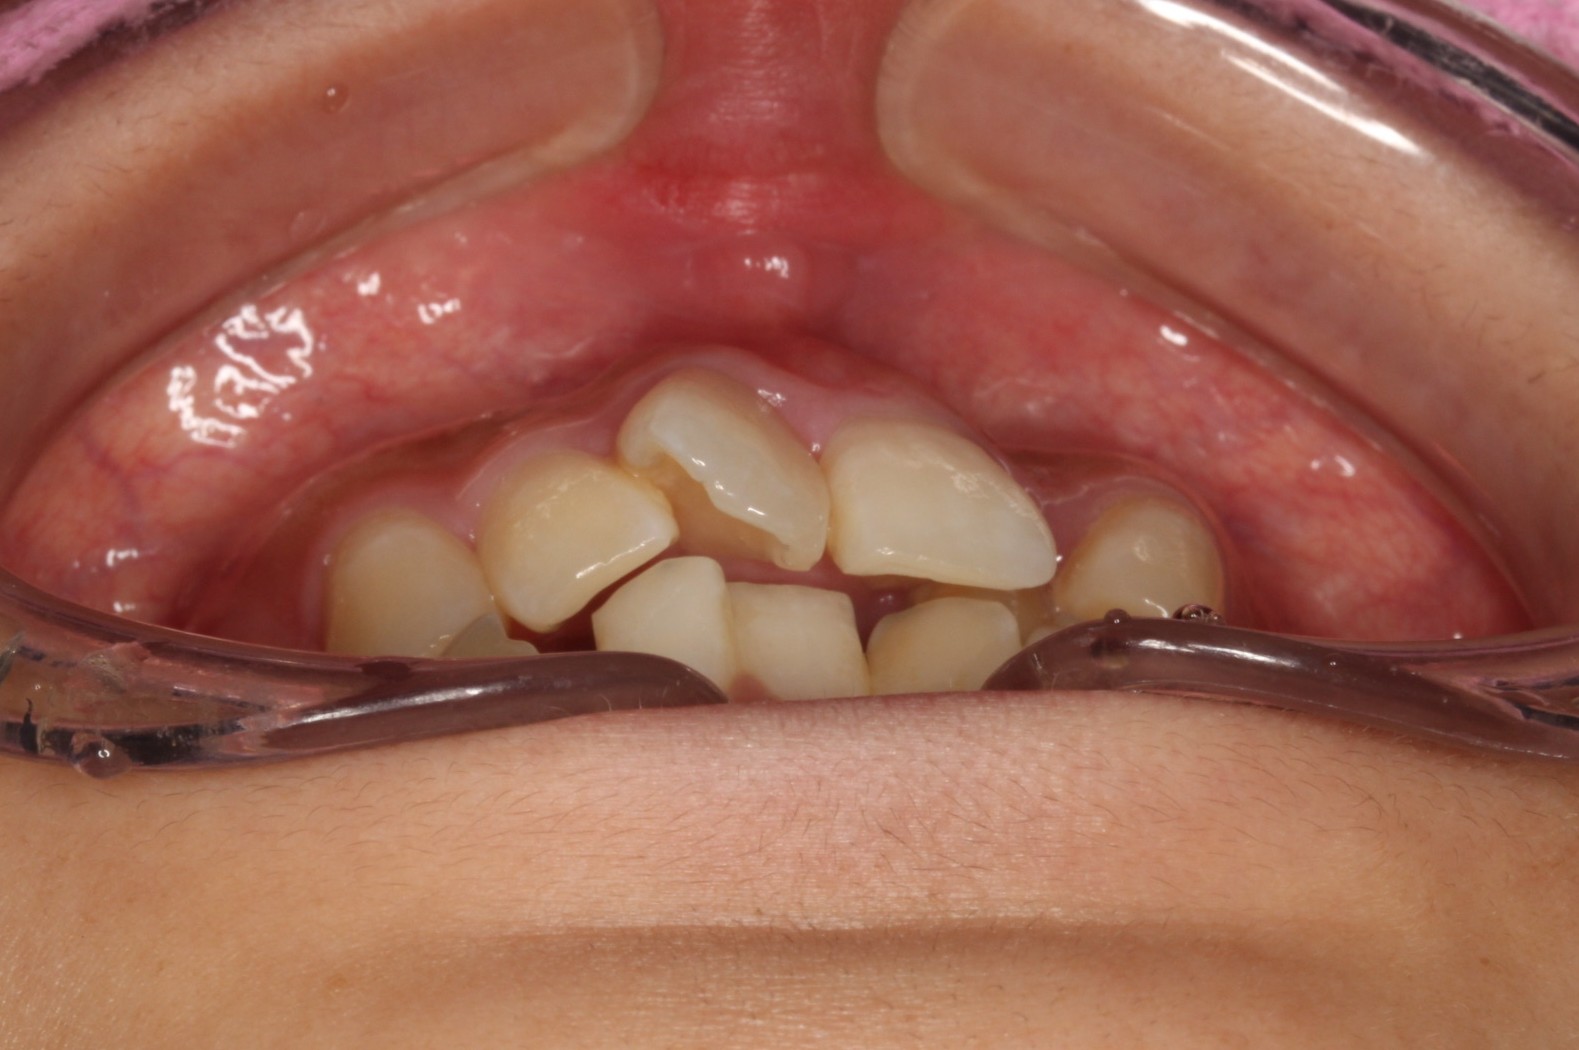

矯正術前:前歯部あおり

今回ご紹介する患者様は、上下のがたつきを気にされており、矯正検査後叢生Ⅰ級と診断いたしました。

矯正前に、上下小臼歯4本を抜歯いたしました。また、ワイヤー矯正後に、インビザラインで仕上げ矯正を行いました。